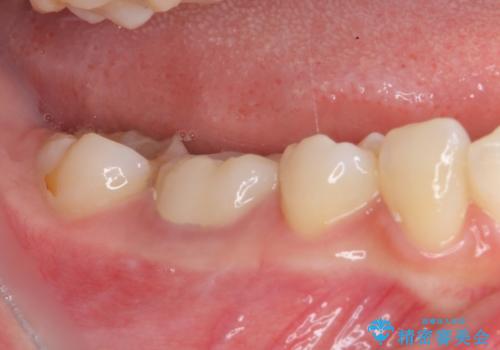

前医での根管治療の度に感じていた痛みの原因は分かりませんでしたが、元々違和感すらなかった歯であったので、速やかに根管治療を行った後に、ジルコニアクラウンを装着しました。

咬み合わせが強く、歯の高さが非常に低かったため、審美性には劣るものの、高強度であるフルジルコニアクラウンを採用しました。